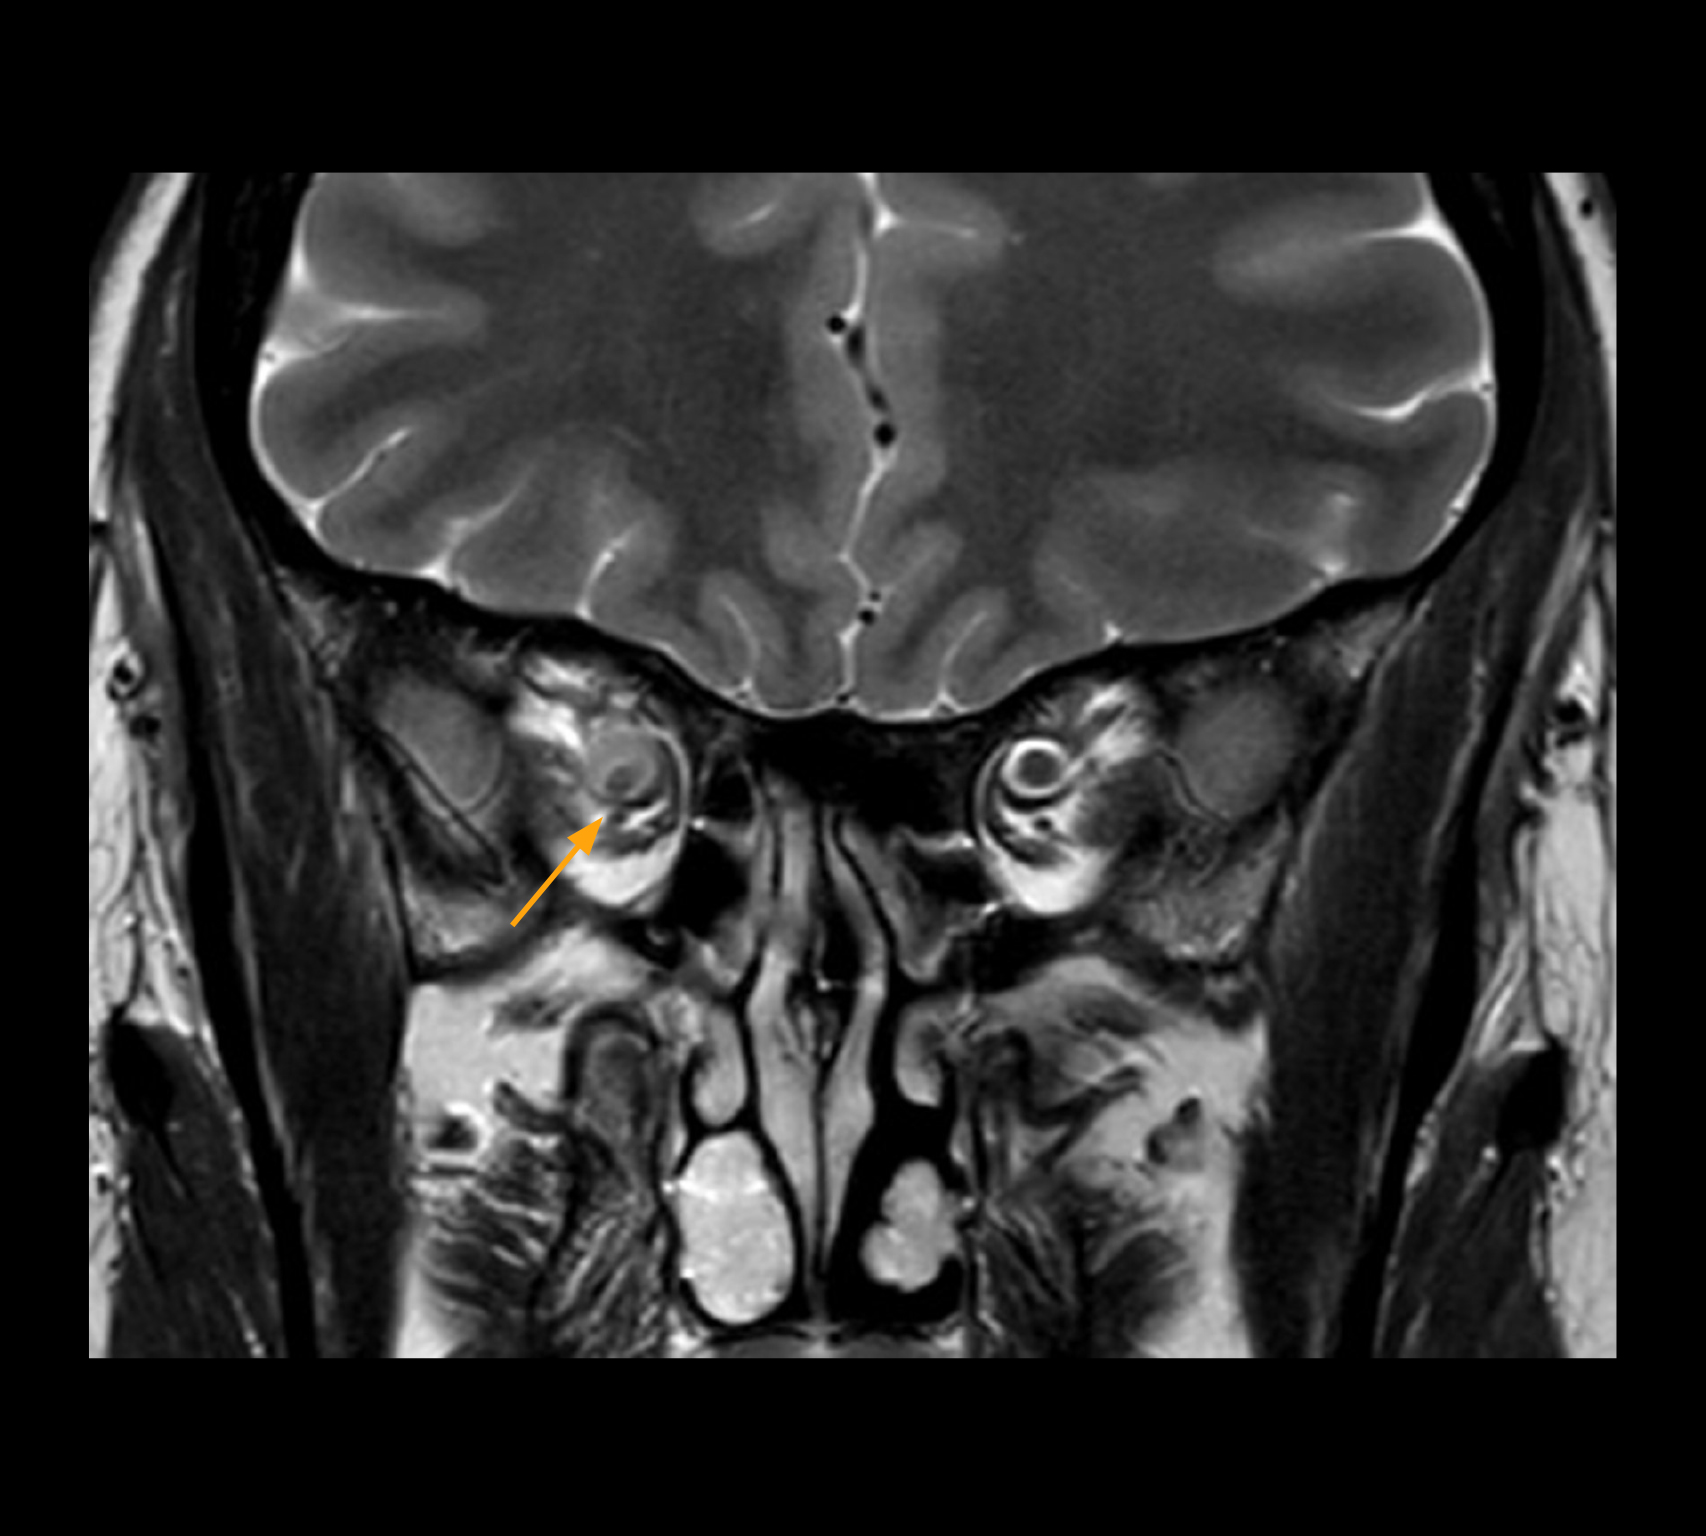

Imaging of the optic nerve sheath

High-resolution MRI impressively demonstrates the compression and narrowing of the right optic nerve in this case of optic nerve sheath meningioma (ONSM). The coronal T2-weighted images show the hyper-intense, half-moon shaped lesion, that is clearly visible in the axial T1W image after contrast injection (right). These imaging findings were so convincing that there sponsible neurosurgeon did not consider a pretherapeutic histological clarification.

Imaging of the optic nerve sheath

High resolution-MRI impressively demonstrates the compression and narrowing of the right optic nerve in this case of optic nerve sheath meningioma (ONSM). The coronal T2-weighted images show the hyper-intense, half-moon shaped lesion, that is clearly visible in the axial T1W image after contrast injection (right). These imaging findings were so convincing that there sponsible neurosurgeon did not consider a pretherapeutic histological clarification.